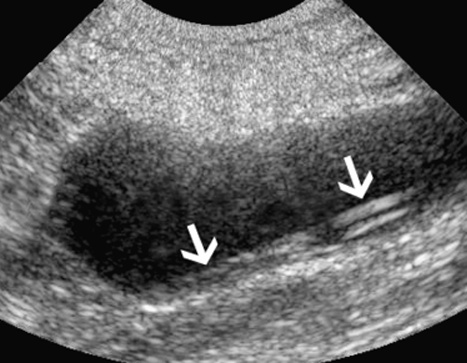

요의 정체(urinary stasis)와 그에 따른 감염은 농신증(pyonephrosis)으로 이어질 수 있습니다. 농신증은 문자 그대로 신우 안의 고름을 의미하며, 고양이에서 요관결석(ureterolithiasis)이 있는 경우 및 대정맥후 요관(circumcaval ureter; 선천성 기형으로 요관이 후대정맥의 뒤쪽으로 감겨들어 간 상태)이 있었던 단일 증례에서 보고된 바 있습니다.

초음파 소견으로는 신우 내 고에코성 잔사(찌꺼기), 수신증, 정상 신장 구조 소실 등이 포함됩니다(그림 4).